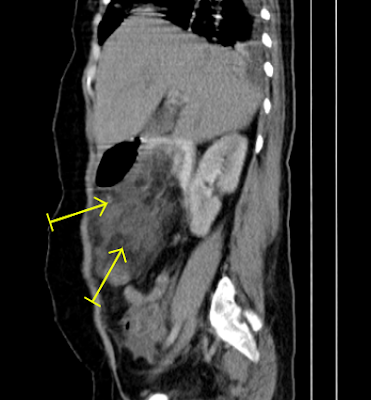

• About 9x6cm  fat containing mass in the right upper abdomen close to stomach         and pancreas with surrounding peritoneal

• fat stranding. DDx: Lipoma/ gastric lipoma?

• Mild ascites with both pleural effusions.